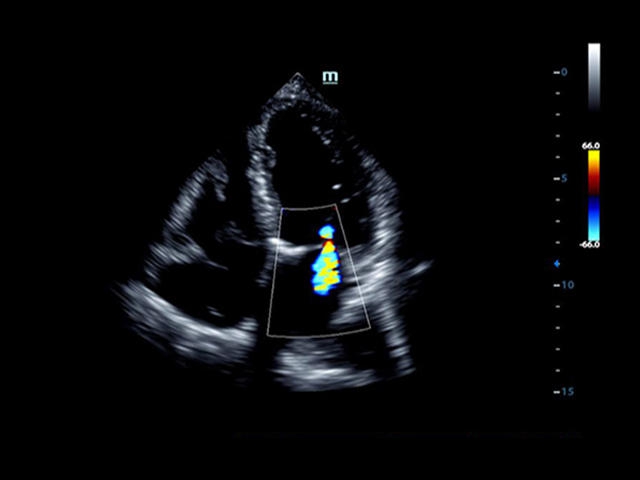

• LVO - опция проведения исследования левого желудочка сердца с применением контрастных веществ;

Кардиология:

• LVO - опция проведения исследования левого желудочка с применением контрастных веществ

• Cardiac package - предустановленные параметры, аннотации, маркеры, программы измерений для кардиологии